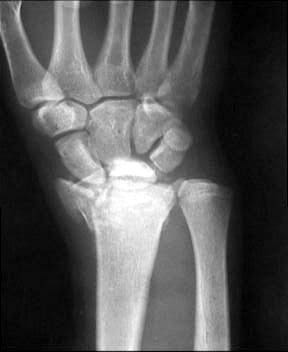

Перелом Barton

Больной из соседнего района 17 лет получил травму 8 09 03. Перелом по классификации E.Muller -В2

Неполный внутрисуставной перелом лучевой, тыльного края (Barton) Наложена гипсовая повязка рис 08 09. Через месяц на контрольной рентгенограмме найдено вывих л\з сустава. Рентгенограмма при обращении в нашу больницу 21 10 03 рис 21 10. На данные момент имеется умеренно выраженная контрактура, умеренные нейровегетативные нарушения. Обдумываем несколько вариантов лечения: 1) Продолжить консервативное лечение и провести артродез, если останется болевой синдром. 2) Провести открытую репозицию, устранить вывих, фиксировать отломок пластиной по тыльной поверхности. 3) Провести артродез в лучезапястном суставе